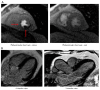

Background: Noninvasive imaging methods, either anatomical or functional tests, serve as essential instruments for the appropriate management of patients with established or suspected coronary artery disease (CAD). We sought to evaluate the safety and efficacy of a coronary computed tomography angiography (CCTA) plus stress cardiac magnetic resonance imaging (S-CMR) strategy in patients with chronic coronary syndrome (CCS). Methods: Patients with suspected CCS showing intermediate coronary plaques (stenosis 30-70%) at CCTA underwent S-CMR. Patients with a positive S-CMR were referred to invasive coronary angiography (ICA) plus instantaneous wave-free ratio (iFR), and myocardial revascularization if recommended. All patients received guideline-directed medical therapy (GDMT), including high-dose statins, regardless of myocardial revascularization. The primary endpoint was a composite of death from cardiovascular causes, non-fatal myocardial infarction, and unplanned revascularization. Results: According to the results of CCTA, 62 patients showing intermediate coronary plaques underwent S-CMR, which was positive for a myocardial perfusion deficit in n = 17 (27%) and negative in n = 45 (73%) patients. According to the results of ICA plus iFR, revascularization was performed in 13 patients. No differences in the primary endpoint between the positive and negative S-CMR groups were observed at 1 year (1 [5.9%] vs. 1 [2.2%], p = 0.485) and after a median of 33.4 months (2 [11.8%] vs. 3 [6.7%]; p = 0.605). Conclusions: Our study suggests that a CCTA plus S-CMR strategy is effective for the evaluation of patients with suspicion of CCS at low-intermediate risk, and it may help to refine the selection of patients with intermediate coronary plaques at CCTA needing coronary revascularization.